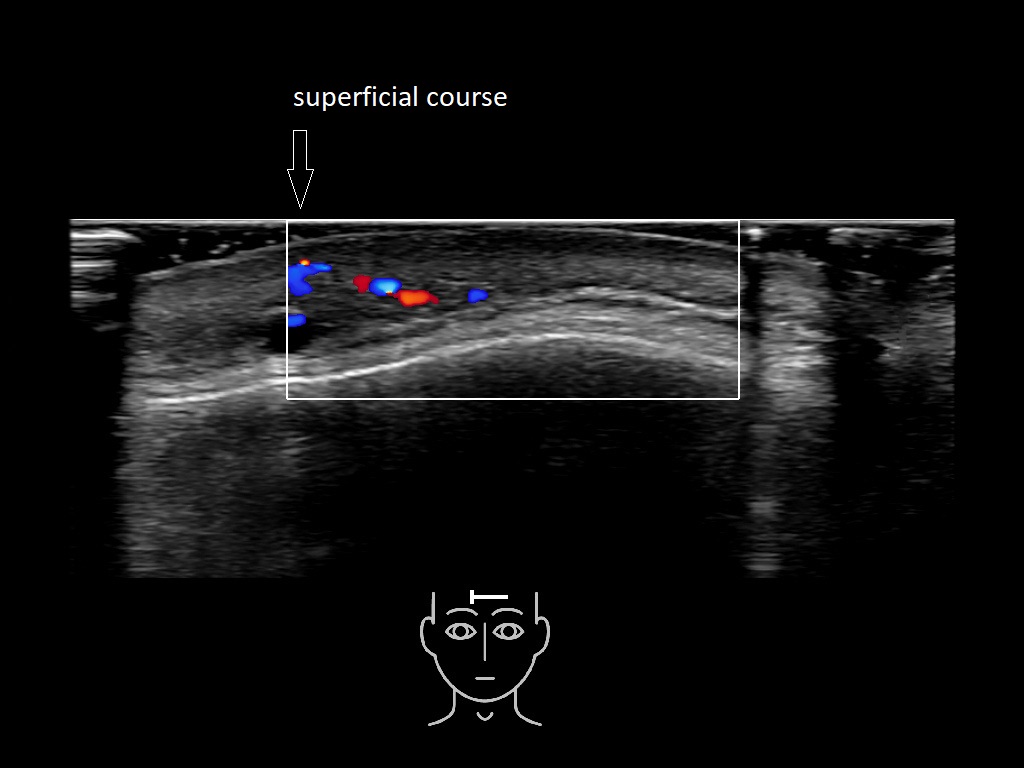

In this section you will learn more about the different layers of the face with the use of ultrasound. When you click on the secondary ultrasound image, you will see the different structures as an overlay. This will help to train yourself to recognize the different layers of the face.

Study the first image to recognize the different layers. If you are sure about the layers, swipe to the second image to view the answer (if applicable).